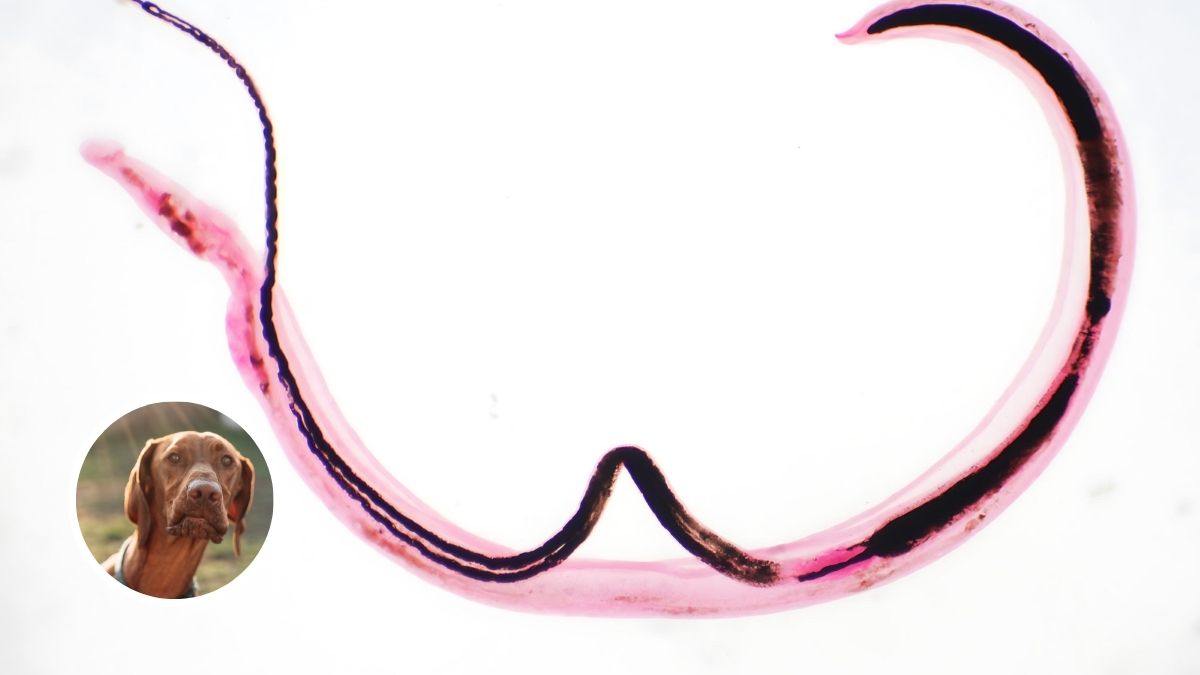

1. Heartworms

Heartworms are large parasites that live in the heart or lungs of your pet and may cause coughing up blood, weight loss, fainting, and weakness. Heartworm disease can be fatal in later stages, but your dog may show no symptoms at first. Mosquito bites are the usual source of heartworm and may infect dogs and humans alike.

Treatment: Heartworm disease happens over several months and needs several medicines to treat over a period of time. The dog must be well rested while he gets treated to avoid complications from killing the worms. Thankfully, this disease can be easily avoided by keeping your area mosquito-free, which will protect both you and your dog.